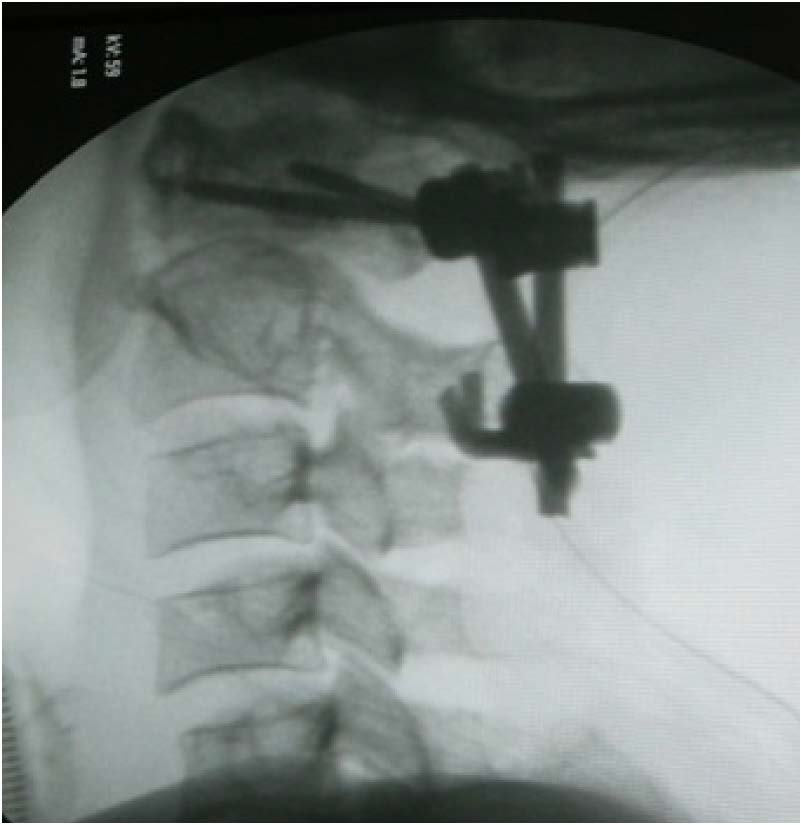

Figure 2: Type II odontoid fracture, Obav, treated by posterior approach. Cervical profile radiograph the screw-hook-rod technique interconnecting polyaxial screws at C1 and hook inserted in contact with the caudal border of C2 lamina with rods.

figure 2